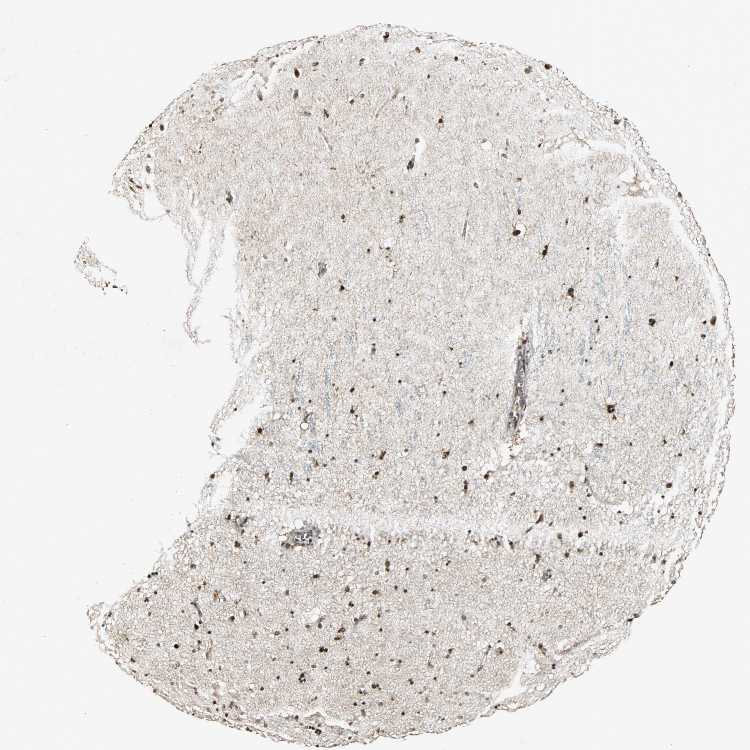

HIPPOCAMPUS - Antibody stainingi

Antibody staining in the annotated cell types in the current human tissue is reported as not detected, low, medium, or high, based on conventional immunohistochemistry profiling in selected tissues. This score is based on the combination of the staining intensity and fraction of stained cells.

Each image is clickable and will lead to virtual microscopy that enables deeper exploration of all samples and also displays staining intensity scores, fraction scores and subcellular localization as well as patient and tissue information for each sample.

Antibody HPA006195Antibody HPA006474

Glial cells HighHigh

Neuronal cells HighHigh